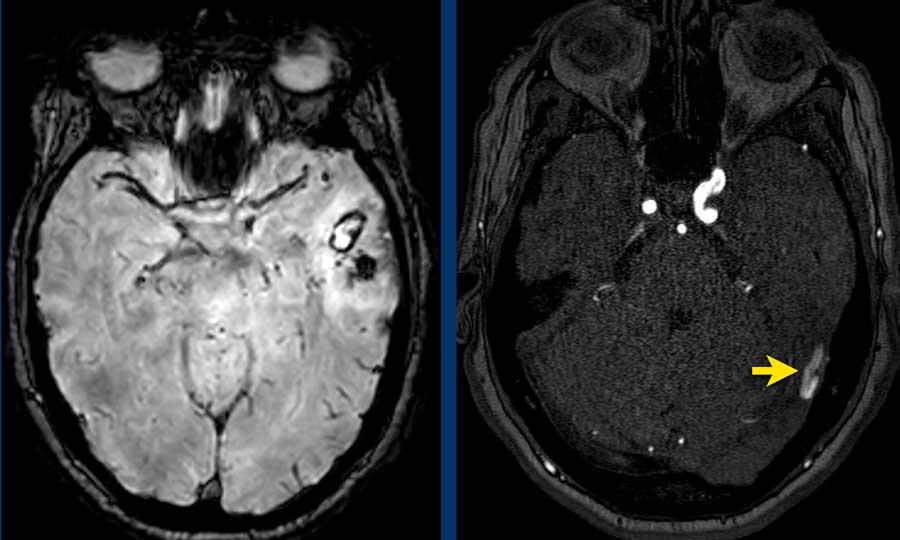

Bệnh nhân nam 55 tuổi nhập viện với triệu chứng đau đầu cấp tính và rối loạn ý thức.

NCCT cho thấy xuất huyết nhu mô thùy não được bao quanh bởi phù não (hình bên trái).

CTA chỉ cho thấy một vài chấm thuốc cản quang (mũi tên) trong khối xuất huyết, kết nối với các mạch máu nhỏ bất thường (không hiển thị) bên dưới khối xuất huyết.

Không quan sát thấy động mạch nuôi hay tĩnh mạch dẫn lưu.

Hiệu ứng khối của khối xuất huyết có thể che khuất nguyên nhân tiềm ẩn trong giai đoạn cấp tính.

DSA và hình ảnh 3D từ động mạch cảnh trong phải cho thấy AVM tiềm ẩn.

- Động mạch nuôi – đầu mũi tên đen

- Nidus của AVM – mũi tên vàng

- Tĩnh mạch dẫn lưu – mũi tên xanh dương

Spetzler-Martin độ 1

- AVM nhỏ < 3cm

- Vùng não không chức năng quan trọng

- Dẫn lưu tĩnh mạch nông

DSA kiểm tra sau phẫu thuật cắt bỏ AVM không còn dấu hiệu tổn thương tồn dư.